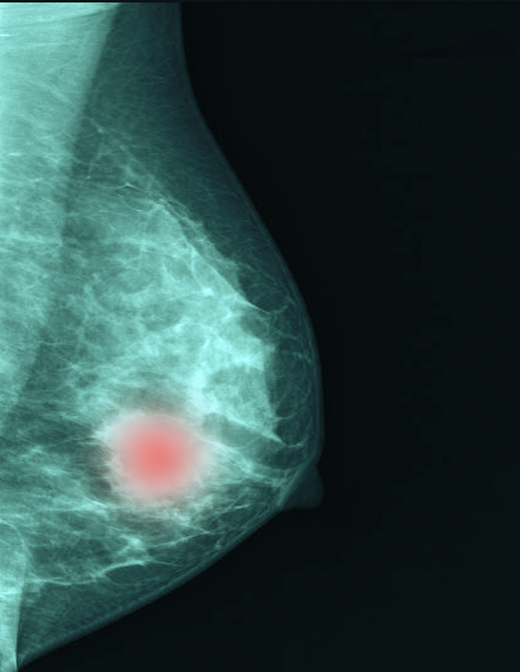

유방암 환자의 60~75%는 에스트로겐수용체(ER)에 양성(+)을, 인간표피성장인자수용체2(HER2)에 음성(-)을 띤다(ER+/HER2-). 이런 유형의 유방암은 초기 치료 성적은 좋지만, 수술 후 5년이 지나면 암이 계속 발생(재발)하는 게 단점으로 꼽힌다. 또 이들은 호르몬 치료를 받았더라도 20년간 누적 재발률이 최대 40%에 달한다.

이에 연구팀은 2000~2011년 수술받은 45세 이하 ER+/HER2- 유방암 환자 중 5년간 재발하지 않은 1701명을 분석했다. 그중 108명(6.3%)은 수술 5~10년에 유방암이 원격 전이해 재발했다.